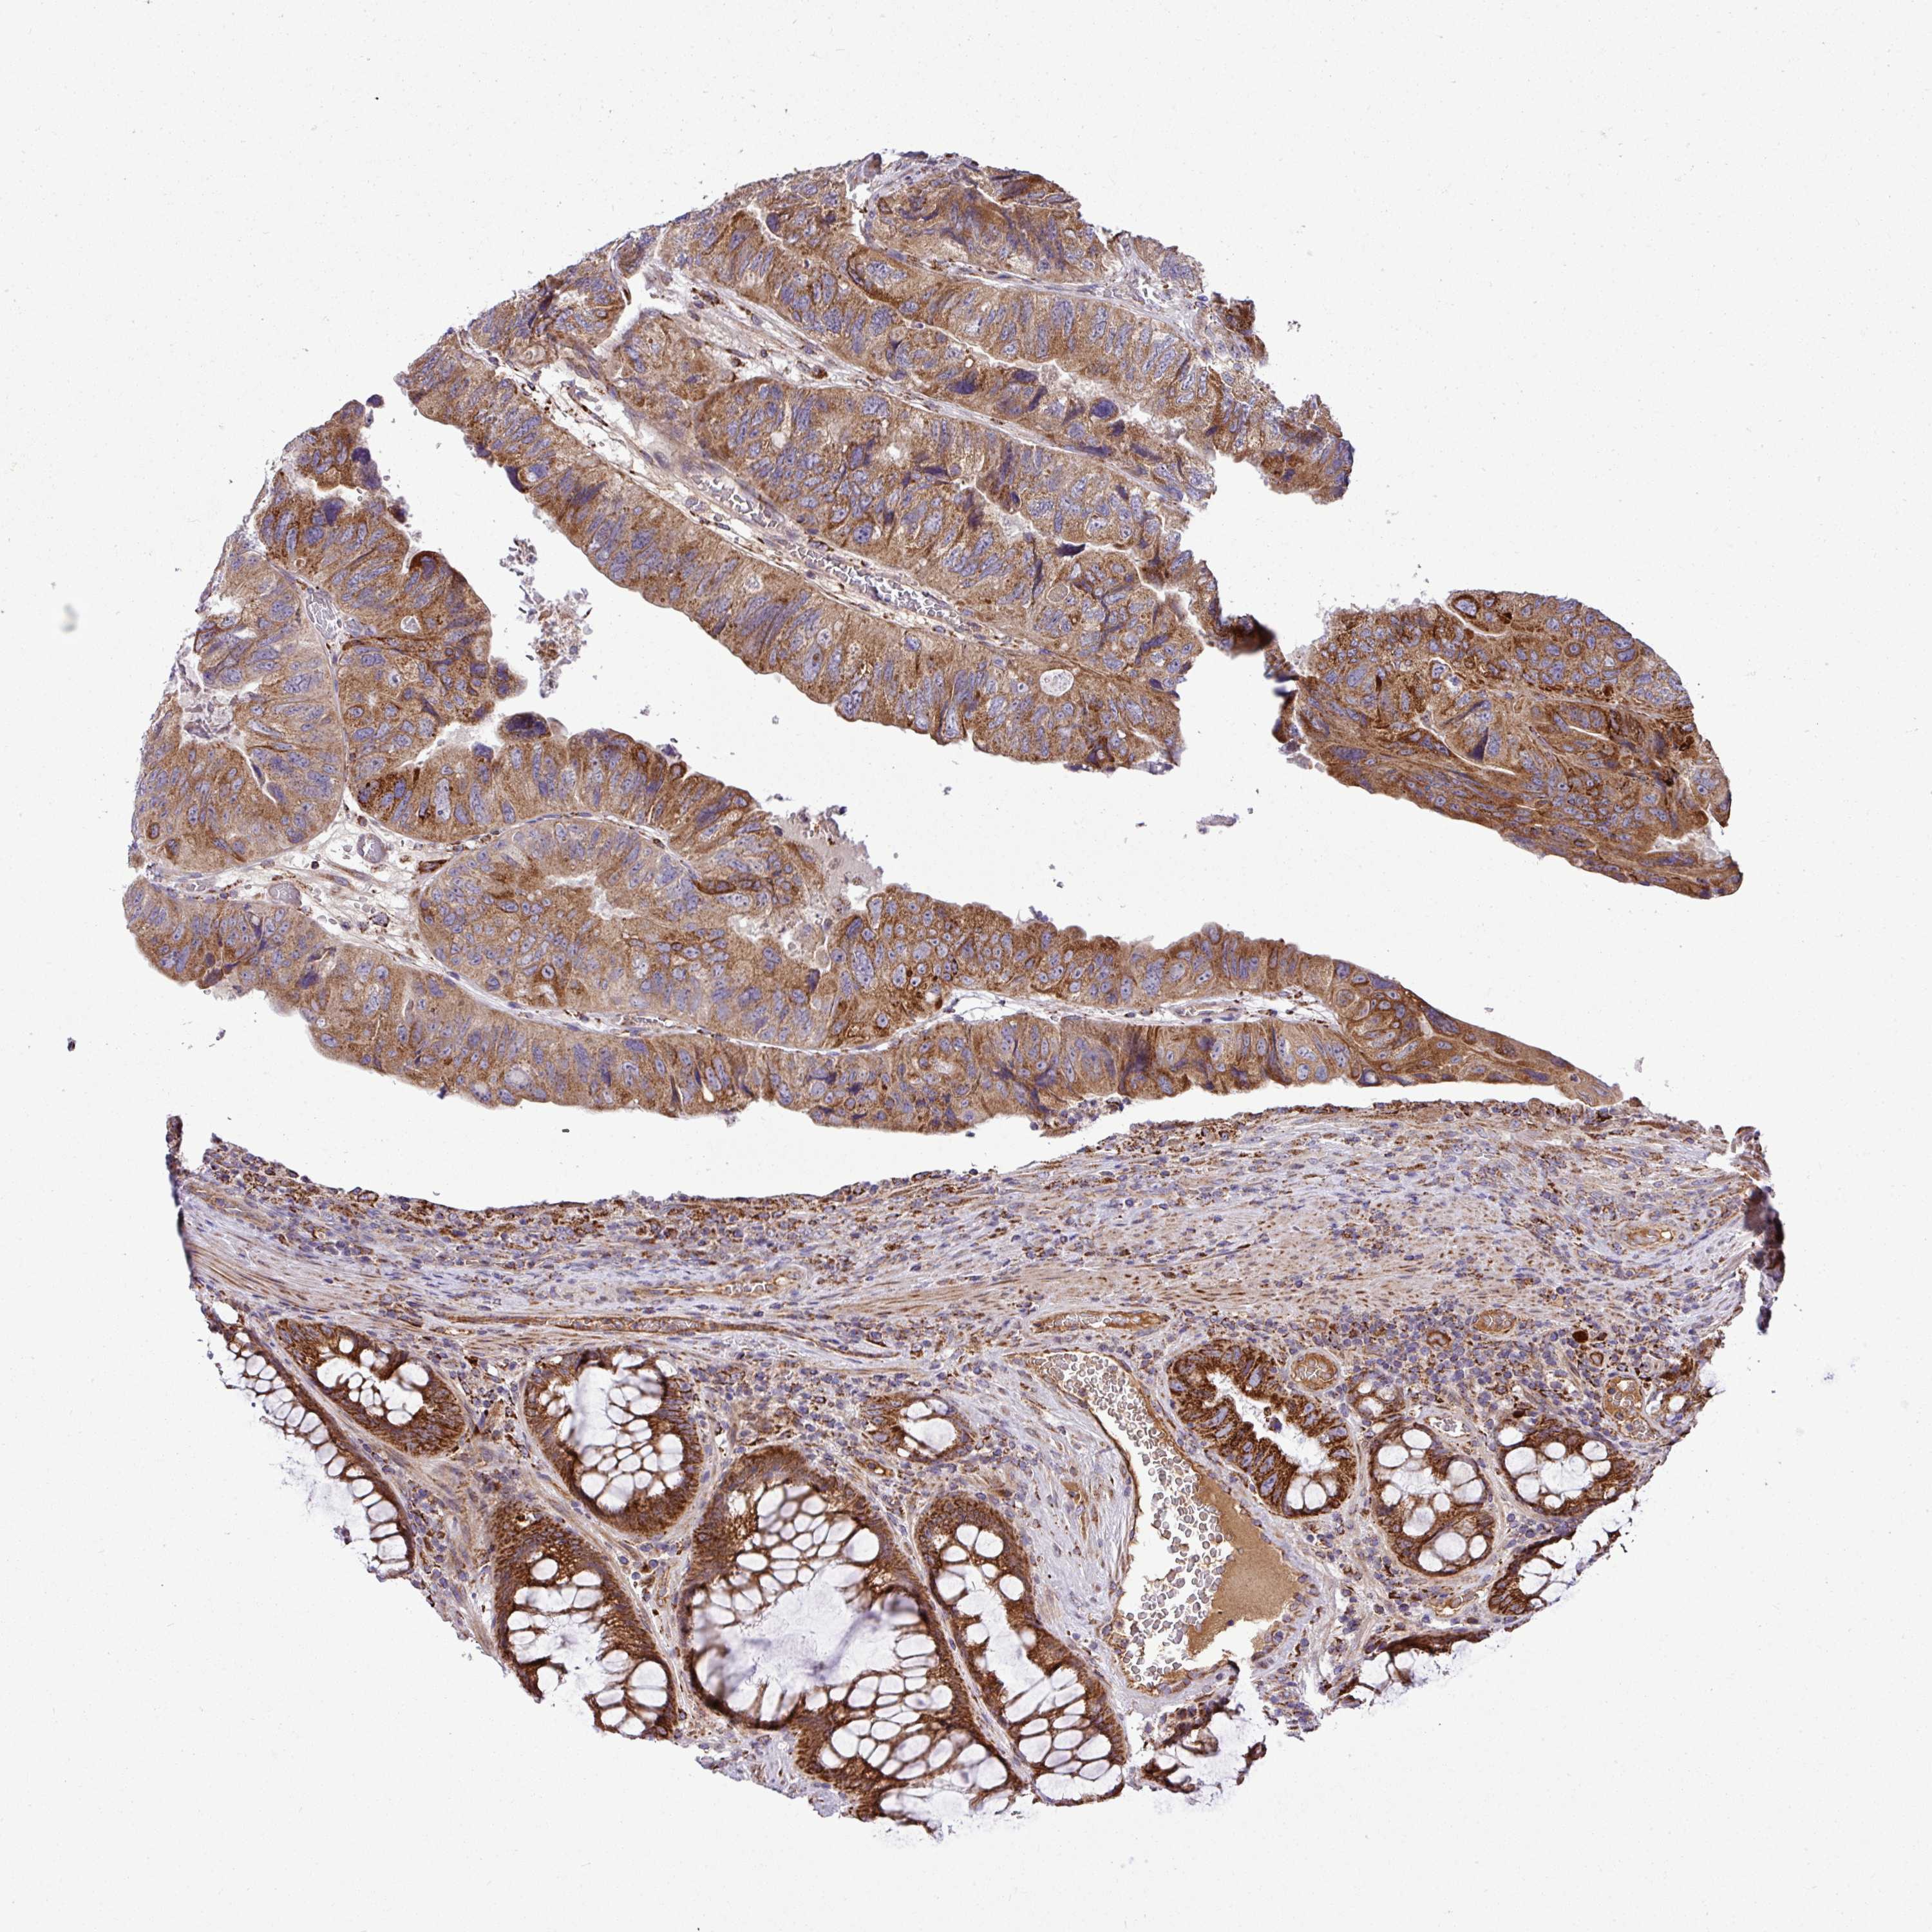

CANCER COLORECTAL CANCER Show tissue menu

Colorectal cancer

Human cancer

Colon adenocarcinoma